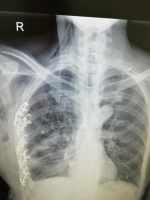

多發(fā)傷并創(chuàng)傷性濕肺 關(guān)鍵疾?。?a href="http://m.akellydesign.com/tags/so/創(chuàng)傷-4-1.html" target="_blank">創(chuàng)傷 現(xiàn)病史【一般資料】男性,60歲,農(nóng)民【主訴】外傷后意識模糊1月余,胸悶5天,加重1天【現(xiàn)病史】1月前患者因車禍導(dǎo)致全身多發(fā)外傷,呼之不應(yīng),車禍現(xiàn)場不祥,急診送某市第二人民醫(yī)院,急查頭顱、胸部CT示:顱腦損傷、胸部多發(fā)骨折,腹部彩超:左側(cè)胸腔積液、脾挫裂傷,診斷為“多發(fā)傷、創(chuàng)傷性休克、重型顱腦損傷、蛛網(wǎng)膜下腔出血、腦室出血、雙側(cè)頂葉挫裂傷出血、彌漫性軸索損傷、頭面部軟組織傷、雙眼視神經(jīng)損傷、頸椎骨折、胸部多發(fā)骨折、右側(cè)尺骨骨折、腹部閉合傷、脾破裂、肝挫裂傷、腸系膜挫裂傷、胰腺挫傷、腹膜后血腫、腹腔內(nèi)...